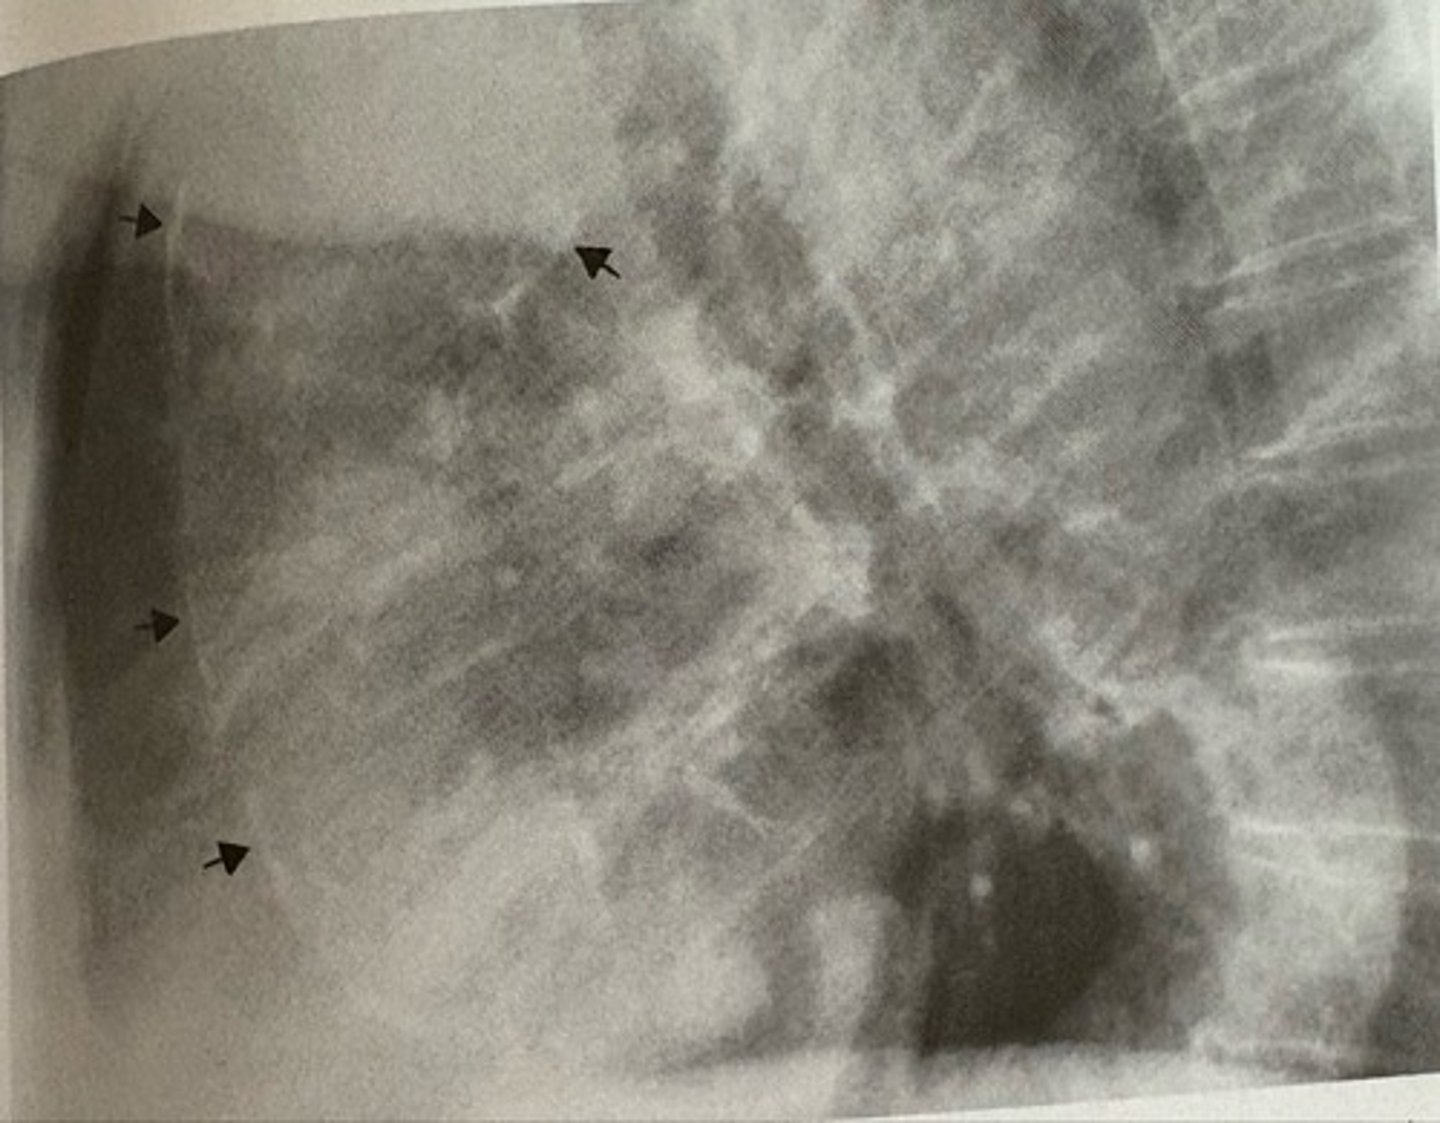

butterfly pattern of severe pulmonary edema

what pathology is present?